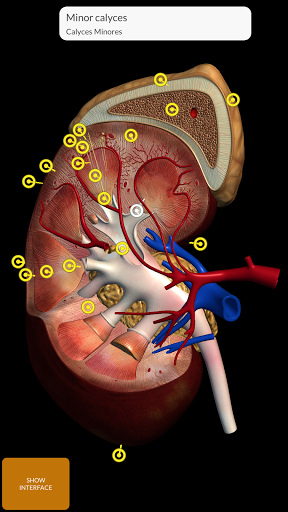

"Anatomy 3D Atlas" дозволяє легко та інтерактивно вивчати анатомію людини.

Завдяки простому та інтуїтивно зрозумілому інтерфейсу можна спостерігати кожну анатомічну структуру під будь-яким кутом.

Анатомічні 3D-моделі особливо деталізовані та мають текстури з роздільною здатністю до 4k.

Поділ за регіонами та попередньо визначені види полегшують спостереження та вивчення окремих частин або груп систем і зв’язків між різними органами.

• Сечостатева система (чоловіча та жіноча)